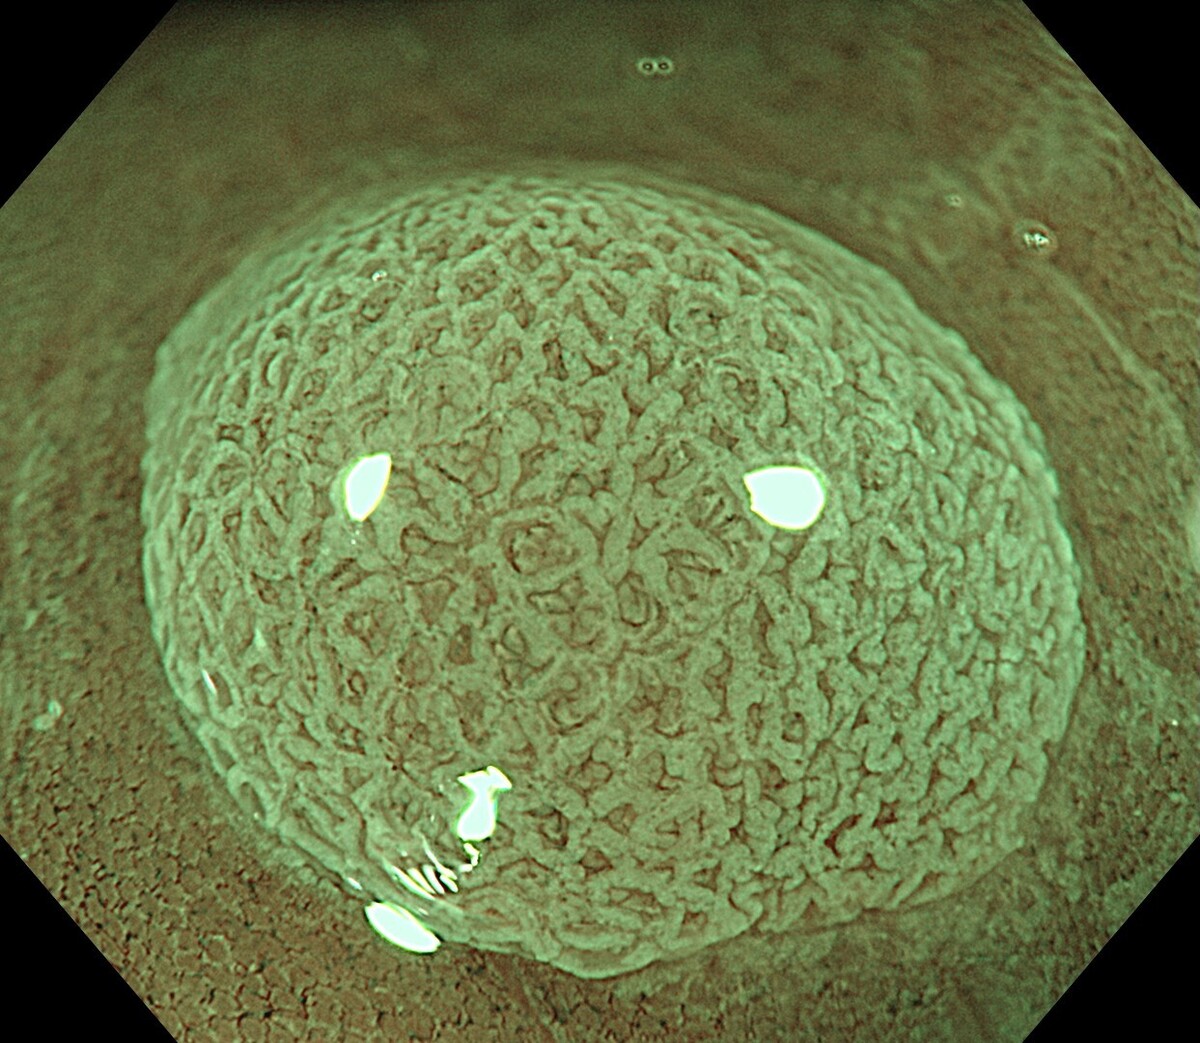

健診:PET-CT、MRI/MRA、胃内視鏡、大腸内視鏡

午前中に胃・大腸内視鏡を行い、午後にFDG-PET/CTを受ける1日完結プランです。PETを含むため、前日または当日の朝にホテルで下剤を服用します。内視鏡で消化管を精査しつつ、PETで全身のがんリスクを可視化できます。特に早期がん、転移、隠れた腫瘍の発見に有効で、全身を網羅的に評価したい方に適しています。

NEO HEALTHCAREは、大阪本町に位置する内視鏡専門クリニックです。 世界トップレベルの内視鏡技術とオリンパス社製の最新内視鏡機器により、最高水準の医療と快適な環境を提供します。

胃または大腸の内視鏡を鎮静下で行い、がん・ポリープ・炎症を精密評価する基本プラン。早期発見を重視し、必要に応じて生検やポリープ切除を追加実施します。

上下部内視鏡検査と全身の超音波検査(頸動脈・心臓・乳腺・腹部・甲状腺)を組み合わせ、消化管から主要臓器までを網羅的に評価する高精度健診プログラムです。

内視鏡に加え、全身のがんを詳細に調べるプレミアムPET/CTを組み合わせた総合がん検査。頭部MRI/MRAや胸部CTなどを含み、主要臓器を一度で網羅的に評価します。